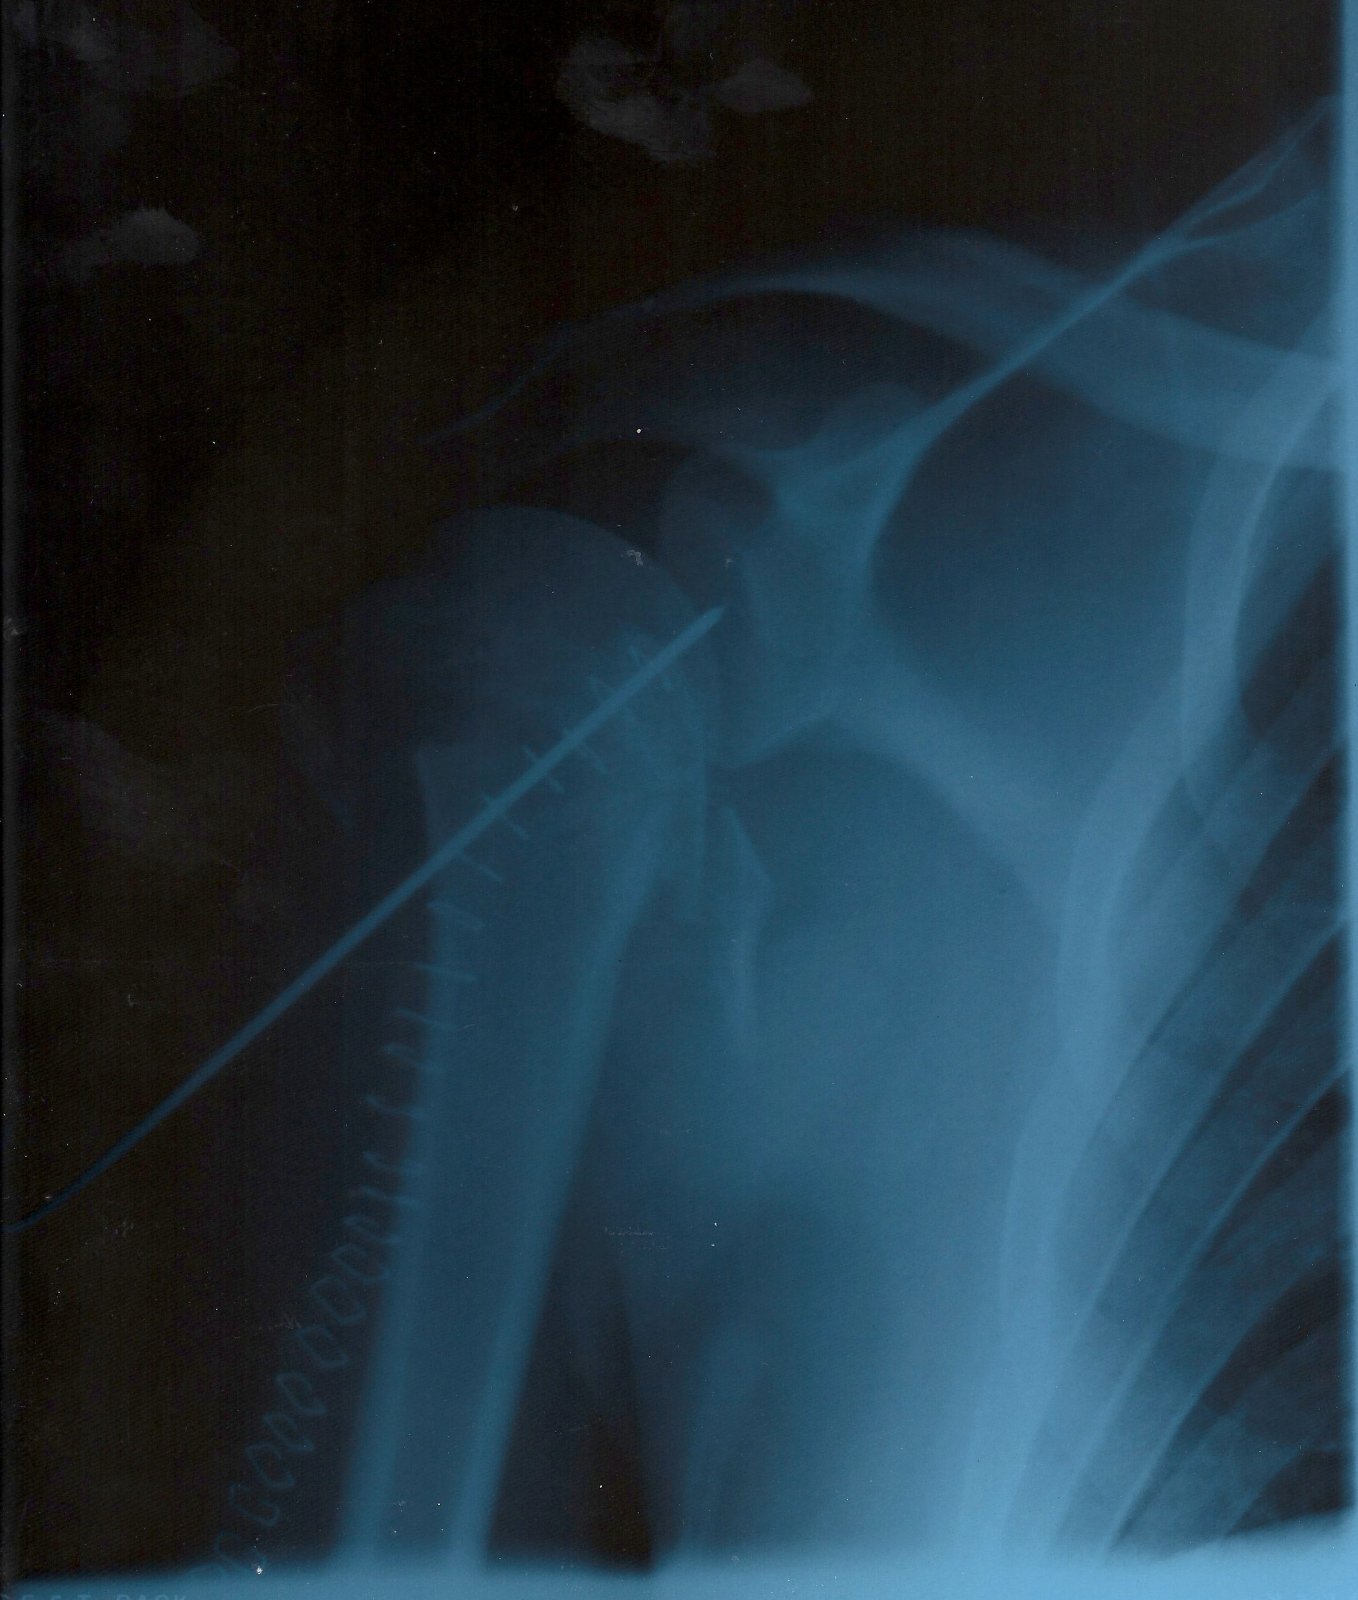

20. OK, I'll give the starter for 10. I decided to come of my 916 in 2001 at a rate of knots. Broke my neck (slightly), hip, rh soulder, rh elbow. 4 weeks in hospital. because I had private health care, my health insurance paid for the x-rays, so I got to keep them.

• 1st pic is my rh shoulder. Surgeon said it was like a digestive that had been hit with a hammer :fearscream:

• 3rd pic is the shoulder with a couple of wires in it and a lot of staples !

Shoulder 1.jpg

Shoulder 2.jpg